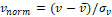

Figure 4: Outliers in the comparison of CNN-TIV (left columns) versus SPM-TIV (right columns) in the reproducibility test set: (a) ADNI subject 002_S_1280 at 1.5T, (b) 052_S_1250 at 1.5 T, (c) 052_S_1250 at 3 T, (d) 133_S_0629 at 1.5T. Displayed images are the TIV segmentations of the first scans in the session, the segmentation results for the second scans were very similar.

Scatter plots of CNN-TIV versus SPM-TIV in the reproducibility test set are shown in Figure 3. There were six outliers at 1.5T: three amongst the first scans and three amongst the second scans (an outlier was defined as the residual deviates from linear regression for more than 3 interquartile ranges (IQR), i.e., below (lower quartile–3*IQR) or above (upper quartile +3*IQR)). There were two outliers at 3T: one amongst the first scans and another amongst the second scans. The outlier(s) amongst the first and second scans referred to the same subjects at both field strengths. The outlier at 3T was also an outlier at 1.5T. Visual inspection of the outliers’ TIV segmentation revealed oversegmentation by SPM12 (Figure 4). In the remaining cases of the reproducibility test set (outliers excluded), CNN-TIV and SPM-TIV were very strongly correlated: Pearson’s correlation coefficient=0.978, 0.977, 0.972, and 0.969 for the first and second scans at 1.5T, the first and second scans at 3T (all P<.001). CNN-TIV estimates were larger than SPM-TIV estimates under all conditions: 67±33ml, 67±33ml, 45±37ml, 45±39ml for the first and second scans at 1.5T, and the first and second scans at 3T (all paired t-test P<.001; Table 1).

The scatter plot of CNN-TIV versus SPM-TIV in the hippocampus test set is shown in Figure 6. There were five outliers, 3 MCI patients and 2 CN subjects. The 2 CN outliers were also outliers in the reproducibility test set, but the 3 MCI outliers were not. Visual inspection of the TIV segmentation revealed over segmentation by SPM12 in all three MCI outliers (Figure 7). In the remaining cases (outliers excluded), CNN-TIV and SPM-TIV were strongly correlated: Pearson’s correlation coefficient=0.981 (P<.001). CNN-TIV estimates were 64±29ml larger than SPM-TIV estimates (outliers excluded; paired t-test P<.001).

Figure 7: Outliers in the comparison of CNN-TIV (left columns) versus SPM-TIV (right columns) in the hippocampus test set: (a) ADNI subject 023_S_0042, (b) 036_S_0976, (c) 109_S_0950.